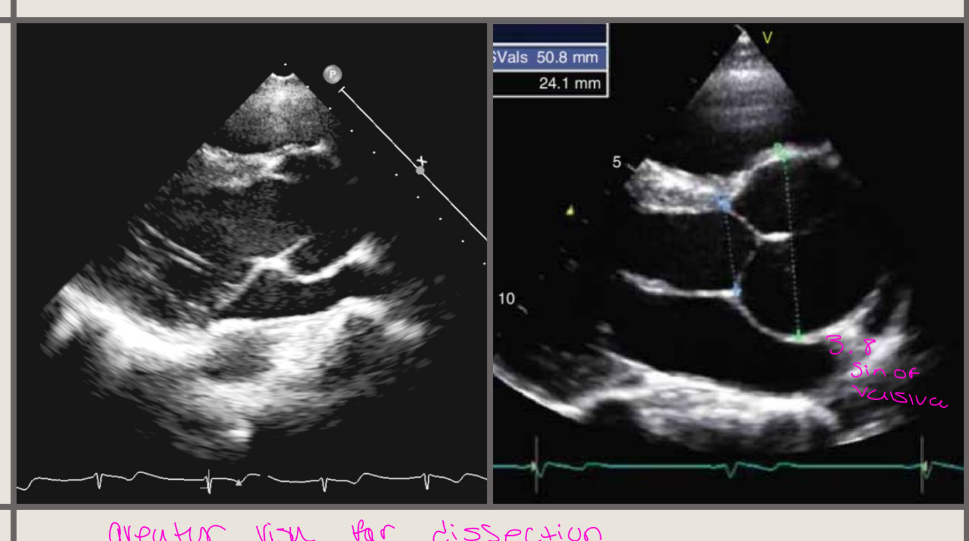

This is best evaluated in what view

In diastole (right), the intra-aortic pressure

forces the aortic valve leaflet to close, but

the unsupported right coronary cusp is

pushed down into the left ventricular

outflow tract away from the opposed

coronary cusp, resulting in regurgitation

This is best evaluated in PLAX

Aortic Dissection what do we always look ?

Always look for the presence and

severity of aortic regurgitation